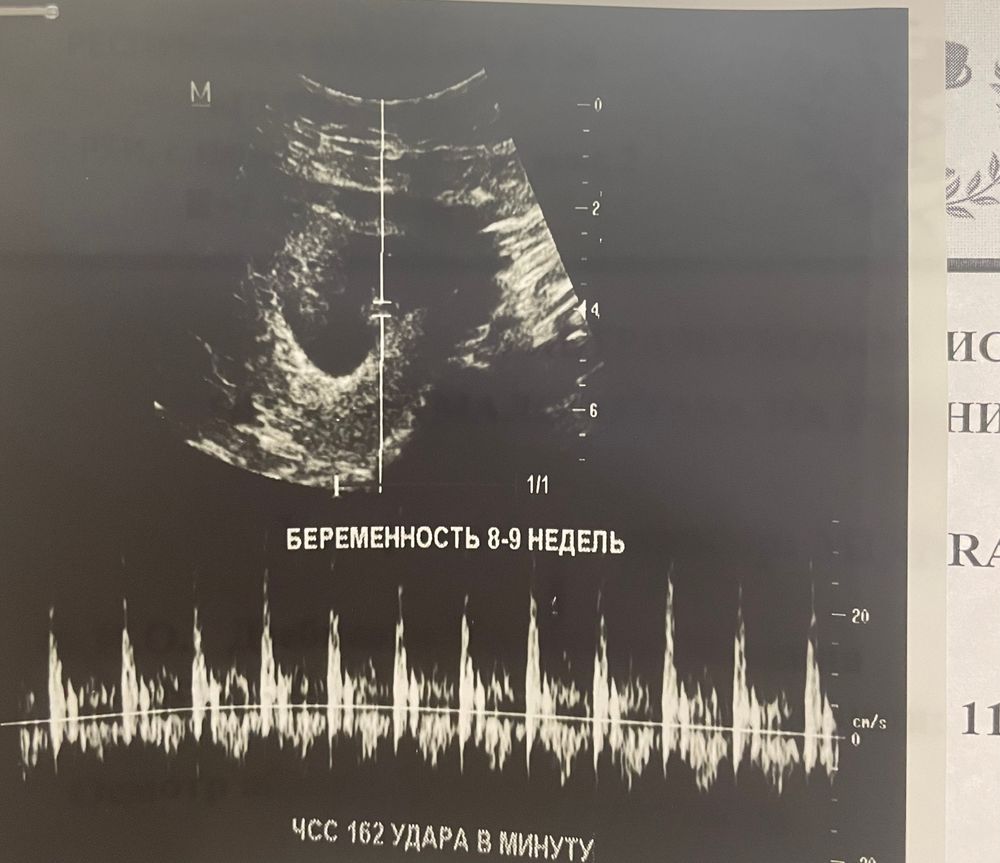

Пол ребенка по Рамзи беременность 8 недель

Может кто подскажет по Рамзи пол ребенка

Узи по животу,желтое тело в правом яичнике